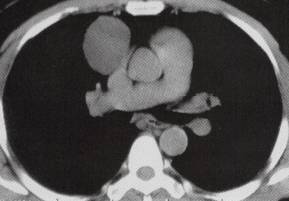

C.D.CT增强扫描示上腔静脉前方囊性占位未见强化,其内密度均匀,呈水样密度,边界清晰锐利;

3.CT表现:心包囊肿表现为圆形、椭圆形或分叶状与心包关系密切,囊肿增大可延伸进入叶间裂,囊肿边缘光滑锐利,囊内密度均匀,呈水样密度,增强扫描无强化,如有感染、粘连则边缘毛糙,囊壁钙化者少见,多呈蛋壳样。

4.CT增强扫描囊性占位未见强化,其内密度均匀呈水样密度,边界清晰锐利。